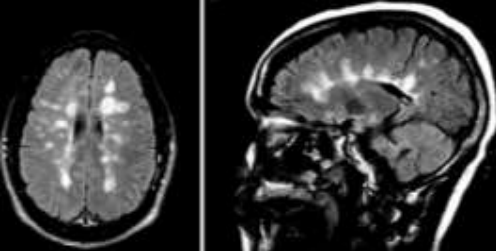

Na imagem abaixo é possível identificar uma lesão expansiva intracraniana sendo a causa provável um meningioma.

Enunciado 3028039-1

Assinale a alternativa correta acerca da classificação topográfica desta lesão.